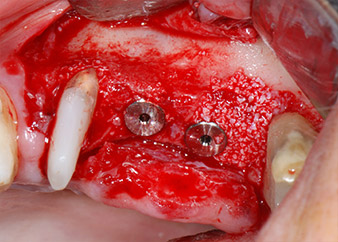

Gli impianti (Restore, Keystone Dental,, diametro 3,75 mm, lunghezza 8,0 mm) sono stati posizionati con il motore per impianto (Figg. 11 e 12).

pronto per le viti di copertura

Fig. 12: Entrambi gli impianti sono posizionati e pronti per le viti di copertura.

Le mancanze di tessuto osseo attorno gli impianti, in corrispondenza dell'aspetto mesiale del dente 27 e attorno alla radice buccale del dente 24, sono stati riempiti con particelle xenogeniche di sostituzione ossea e coperte con una membrana di collagene assorbibile (Bio-Gide, Geistlich Biomaterials) per tecnica di innesto GBR (Figg. 13 e 14).